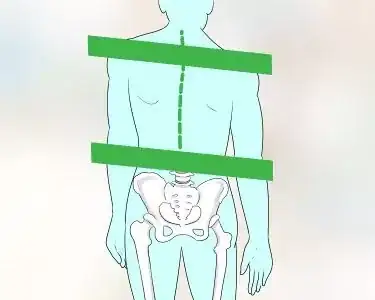

How to

Straighten Your Spine